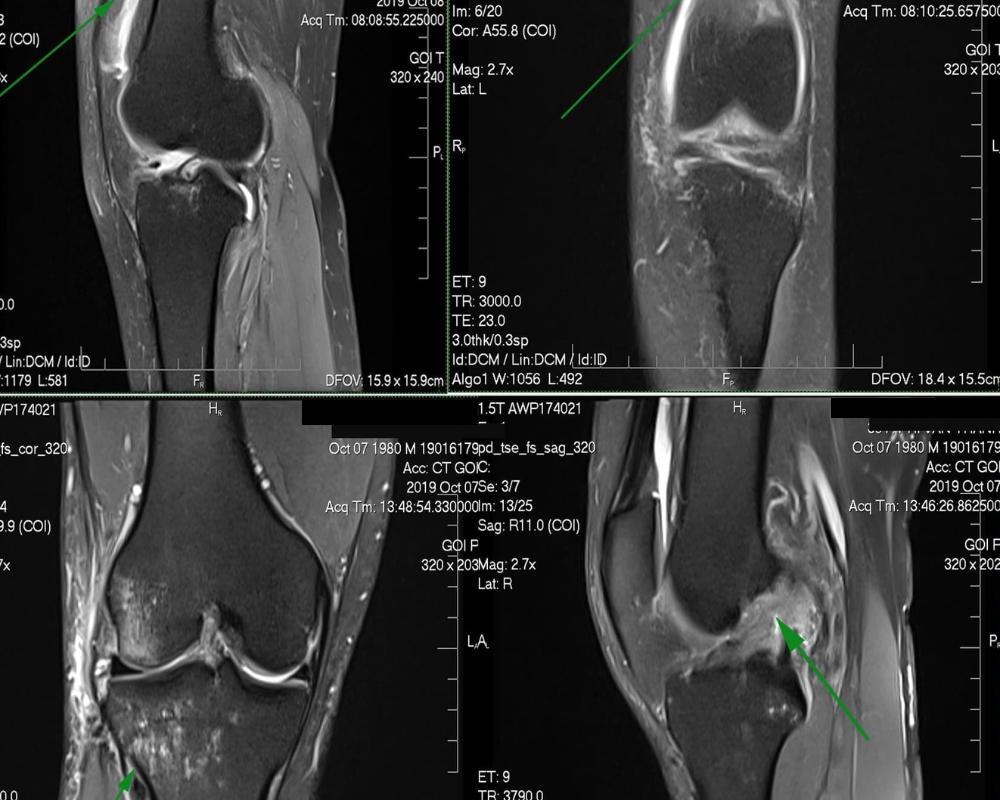

- Chụp cộng hưởng từ MRI: Cho phép quan sát hình ảnh và tình trạng của khớp rõ nét nhất trong không gian 3 chiều, giúp phát hiện được tổn thương sụn khớp, dịch khớp, dây chằng dễ dàng.